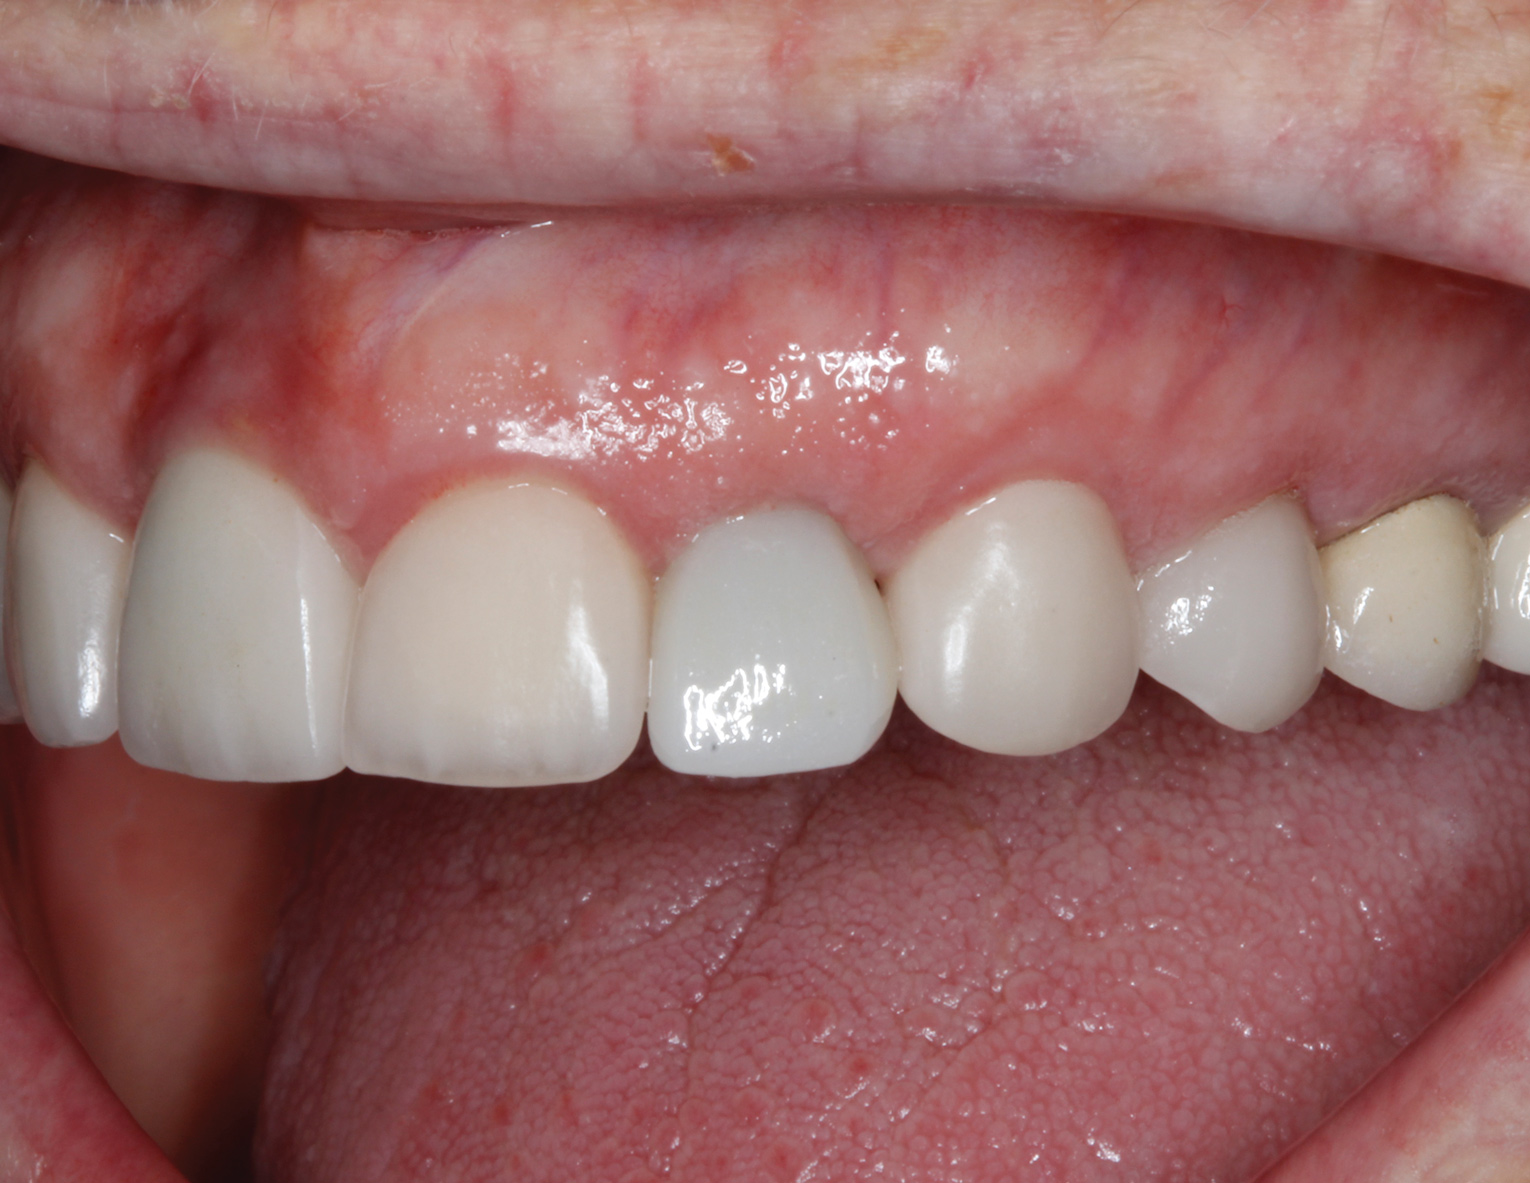

Healing of the site was observed on several occasions post-surgery, including at 4.5 months (Figure 18). Excellent gingival and underlying bone contours were revealed in 24-month photographs and panoramic x-ray (Figure 19 through Figure 21).

Fig 19. Restoration at 24 months, occlusal view (Fig 19) and buccal view (Fig 20).

Figure 19

Fig 20. Restoration at 24 months, occlusal view (Fig 19) and buccal view (Fig 20).

Figure 20